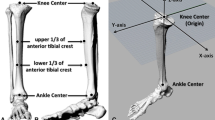

Three-dimensional proximal tibial sclerotic bone models

From January 2018 to January 2019, patients with knee OA and severe genu varum over 15° were selected for 0.6 mm thin-layer CT scanning of both lower extremities and 3-D modelling using Mimics 14.0 (Materialize, Leuven, Belgium) A severe varus OA case’s clinical images were shown in Fig. 1. Patients with rheumatoid arthritis, suspected preoperative infection, or who previously underwent knee surgery were excluded from the study. The following coordinate system was established for the modelling, as shown in Fig. 2: the z-axis was the tibial MA, which was defined as the line connecting the center of the ankle joint and the center of the random axial levels below the articular surface of the proximal tibia and above the tibial tuberosity; the y-axis was defined as the anterior-posterior (AP) axis, which was the connection between the medial edge of the tibial tuberosity and the midpoint of the posterior cruciate ligament after an experienced orthopedist recommended omitting the effect of the osteophyte in the plane perpendicular to the z-axis; the line perpendicular to the y-z axis was defined as the x-axis, and the fibula was disregarded to simplify the model (Fig. 2e). The tibial cut was performed on the plane perpendicular to the tibial MA and 8 mm below the lateral tibial plateau surface. Cases were included in the study if there were no defects in the medial tibia. If there was a defect in the medial tibia less than 4 mm from the tibial cut plane, the amount of lateral tibial cut was increased until the defect was removed, and the case was included. If the medial defect was greater than 4 mm, the case was excluded. Among those 120 cases, 4 cases were excluded from the study based on a preoperative posterior drawer test which was strongly positive (+++) and subsequent diagnosis of posterior cruciate ligament injury. According to these criteria, a total of 116 patients were included in the study. Basic statistical data are shown in Table 1.

The proximal tibial sclerotic bone area of a severe right varum genu from CT images and the distribution obtained by the 3D reconstruction technique. T: top; B: bottom; L: left (medial); R: right (lateral); A: anterior; P: posterior. Blue line: Z axis (Mechanical alignment,); Green line: Y axis(AP axis); Red line: X axis

Within the sample population, the proximal tibial sclerotic bone area was defined as the area with a Hounsfield unit (HU) value of 400–2000 HU in the CT image (based on Mimics software default classification of: bone = 220–2000 HU, compact bone = 660–2000 HU, and spongy bone = 148–661 HU). After auto-selection by Mimics software, the experienced orthopedists and imaging doctors rescreened areas with abnormal HU values from the original cancellous bone after a simulated tibial cut, establishing a 3-D tibial sclerotic bone model (Fig. 2a-c). Since zoning methods such as the whole-organ magnetic resonance imaging score (WORMS) and the magnetic imaging OA knee score (MOAKS) are based on the coronal, sagittal and axial views from magnetic resonance imaging, and the quantitative partitioning could not be accurately performed, we optimized WORMS and MOAKS methods to improve the accuracy of the quantitative partition of the knee on the tibial side [15, 16], as shown in Fig. 2d. For this, a plane perpendicular to the y-axis and another plane parallel to that plane were created. The proximal tibia was equally divided into three portions by the two planes in the x-axis direction. Two planes perpendicular to the existing two planes parallel to the y-axis were created and the two planes were extended toward the y-axis to divide the tibia into three portions equally (Fig. 2d). According to this method, the proximal tibia was divided into the inner anterior region, the inner central region, and the inner posterior region. The sclerotic bone was also divided according to the modified proximal tibial partition. The total volume, sclerotic bone volume in each zone, the relative volume ratio, and the thickness between the tibial cut plane and the distal end of the sclerotic bone were recorded. According to the thickness of sclerotic bone, the models were divided into four types: large (L) = 15 mm, medium (M) = 10 mm, small (S) = 5 mm, and none (N) = 0 mm. The axial distribution of the sclerotic bone models was set according to the mean value of the 3-D measurement distribution ratio. Based on the four types of sclerotic bone models, the different tibial cut angles were categorized. The MA tibial cut was perpendicular to the tibial alignment, and the KA and valgus 3° tibial cut were simulated by 3° varus and valgus rotation of the previous MA tibial cut plane on the x-z coordinate system. Based on the 4 types of tibia and proximal tibial sclerotic bone tibial cut models and 3 groups of alignments, the sclerotic bone models comprised the following 12 variations: L-MA, L-KA, L-valgus 3°; M-MA, M-KA, M-valgus 3 °; S-MA, S-KA, S-valgus 3°; N-MA, N-KA, N-valgus 3°.